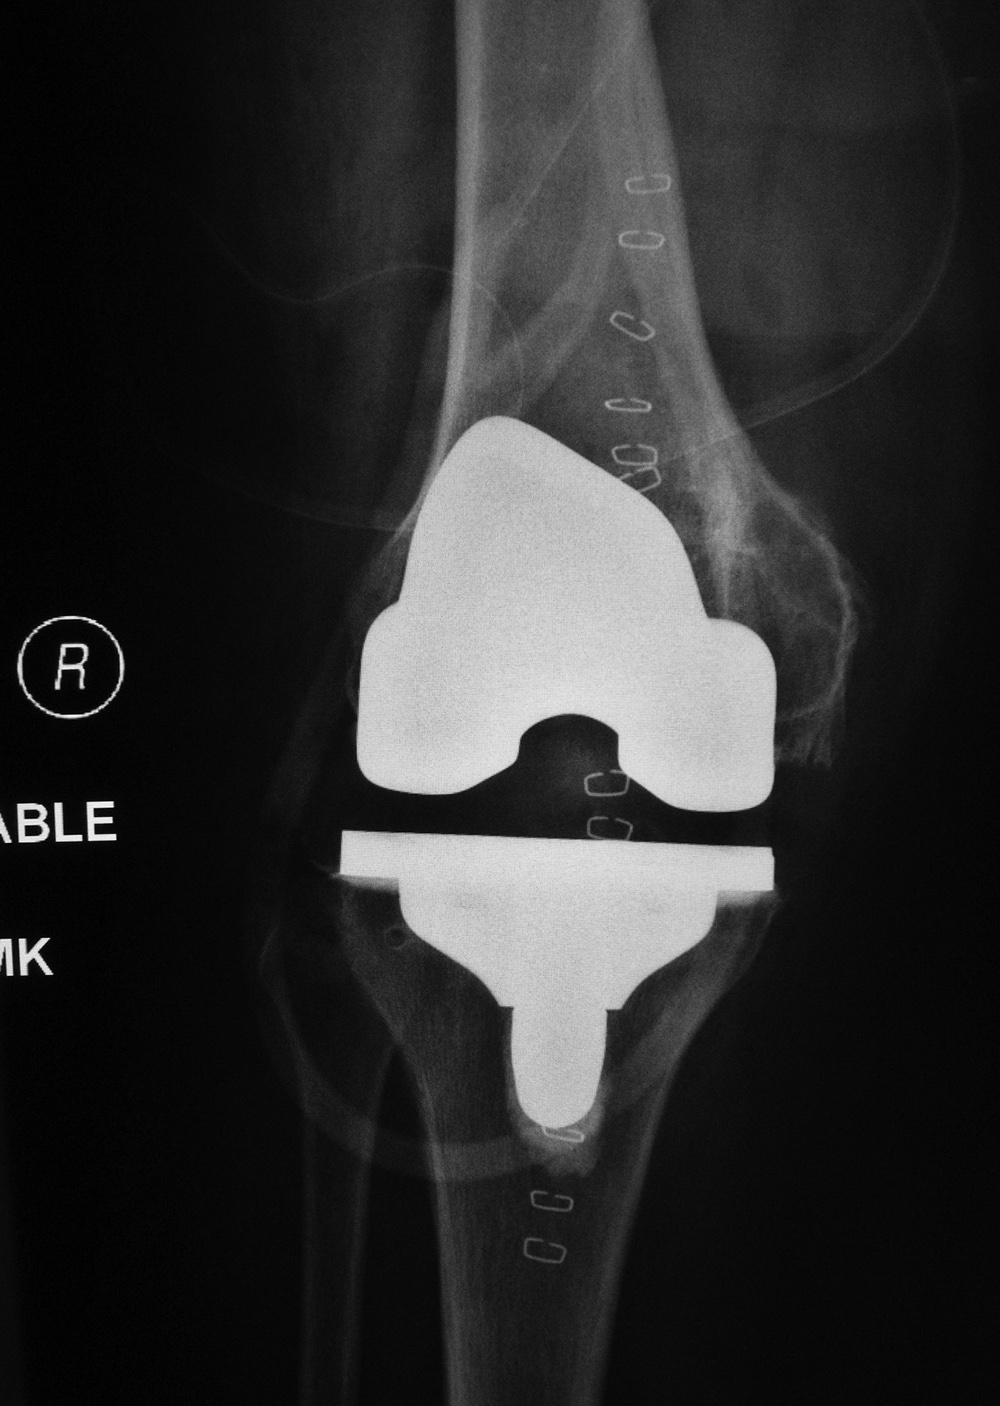

| Posterior cruciate retaining total knee arthroplasty (TKA) |

A PCL-retaining knee allows for preservation of the posterior cruciate ligament and is a relatively unconstrained design (figure: cruciate retaining TKA). For this type of prosthesis to be successful there must be good bone stock, intact surrounding muscles and ligaments, and a posterior cruciate ligament that remains functional (Mulcahy, 2013).